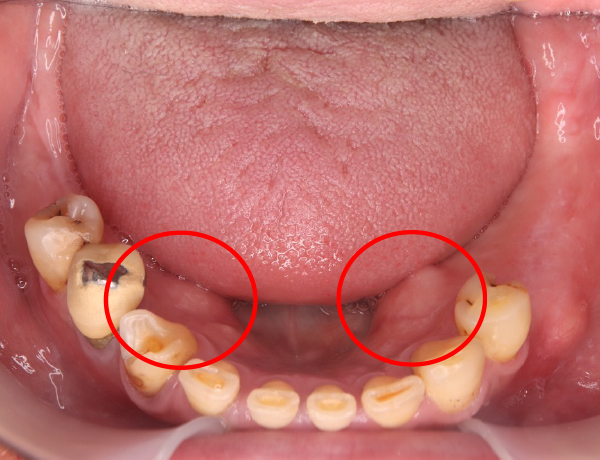

1. 噛む力が非常に強い お口の中には骨隆起が認められました。赤丸で示している部分が、口蓋隆起と呼ばれる骨の盛り上がりです。このような骨隆起がある場合、噛む力が一点に集中しやすく、入れ歯に通常以上の負担がかかります。

左下に入れ歯が入っておらず歯がないので、噛み合わせは左右アンバランスになってますね。赤丸の部分は、骨隆起ですね!噛み合わせの強い方に現れる骨の隆起になります。

赤丸の部分にこれでもかってくらい大きな骨の隆起があります。噛む力がかなり強そうです。

赤丸の部分は、骨隆起になります。下あごにも骨の隆起があります。